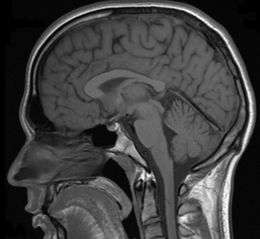

In a case of misdiagnosed depression recounted in Newsweek, a writer received treatment for depression for years; during the last 10 years of her depression the symptoms worsened, resulting in multiple suicide attempts and psychiatric hospitalizations. When an MRI finally was performed, it showed the presence of a tumor. However, she was told by a neurologist that it was benign. After a worsening of symptoms, and upon the second opinion of another neurologist, the tumor was removed. After the surgery, she no longer suffered from depressive symptoms.[28]

In addition to pituitary tumors, tumors in various locations in the central nervous system may cause depressive symptoms and be misdiagnosed as depression.[28][69]